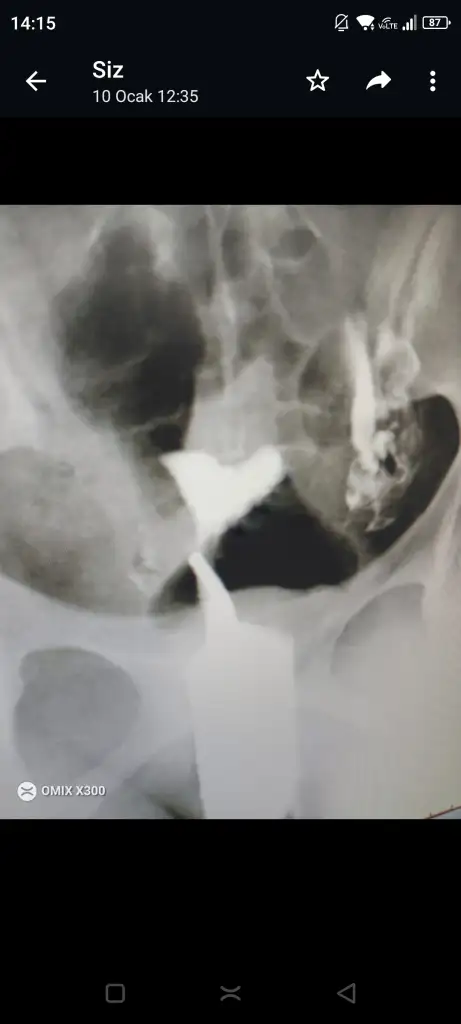

İnşallah canımBu arada seninle konuştuktan sonra rahim filminin görüntüsünü istedim internetten benzerini atmıştım ya şimdi kendi rahim filmim var ekliyorum görüntüyü ben bi karşılaştırma da yaptım benim kendi filmimde rahmim baya baya perde yüzünden daralmış alan kalmamış bebeğe nerdeyse Normal bi rahimle karşılaştırınca benimki ameliyat olmalı teşhisini ben bile koydum kendi kendime

Evet canım bak bebek için bi alan yok biraz çökük olsa onu çok önemsemiyolar ama gözüktüğü gibi baya dar.Kesin ameliyat ol.Arkadasm oldu hc korkulacak bisey yok benm kide dar gbi geliyo bana ama bilmiyorum artk kaç doktora sordum bu şekilde dene dediler.Benimki tam kalp şeklinde üst taraf çökük ama iç alanda bebek icn yer var dediler ynede düşünmeden edemiyorum hamile olnca daha zor.Oyzden ameliyatını ol.Benm rahmde bu.İnşallah canımBu arada seninle konuştuktan sonra rahim filminin görüntüsünü istedim internetten benzerini atmıştım ya şimdi kendi rahim filmim var ekliyorum görüntüyü ben bi karşılaştırma da yaptım benim kendi filmimde rahmim baya baya perde yüzünden daralmış alan kalmamış bebeğe nerdeyse Normal bi rahimle karşılaştırınca benimki ameliyat olmalı teşhisini ben bile koydum kendi kendime